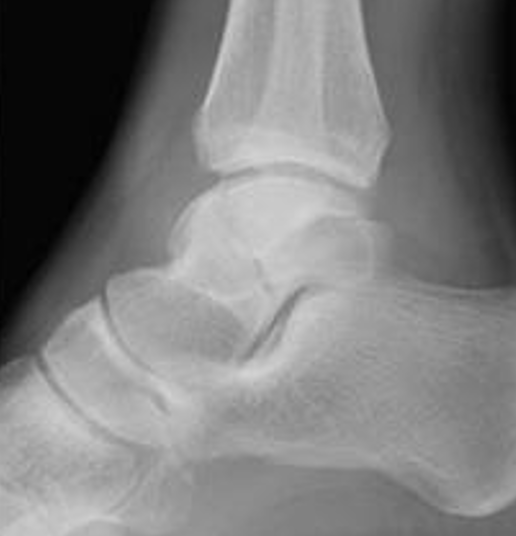

Xray / CT

Ensure no displacement / malalignment

Xrays

| AP | Lateral | Canale View |

|---|---|---|

| Entry point of the screws |

Evaluate neck reduction

|

Evaluates the neck reduction |

Lateral off articular surface Medial through articular cartilage |

Depth of screws |

Beam angled 75o to foot Foot 15o pronated |